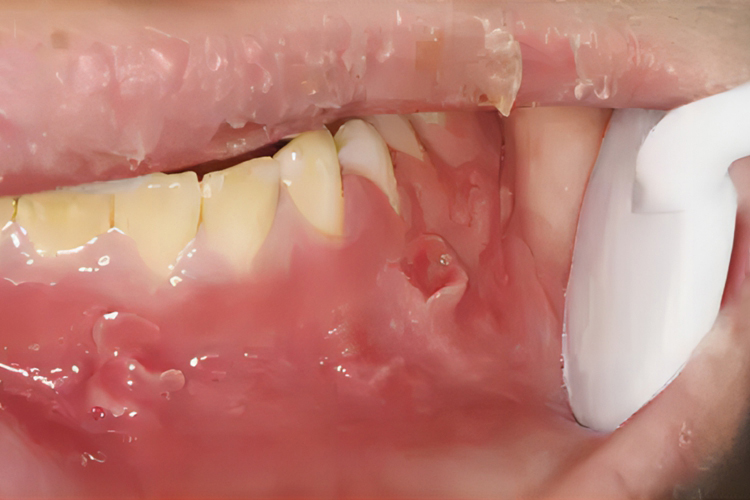

口腔结节是出现在口腔黏膜的突起实体病损,为团块状,迫使表面上皮向外突起,大小不一,一般直径为5cm,形状不定,颜色从粉红至深紫色,可能是克罗恩病、结核性溃疡、卡波西肉瘤等导致,具体如下:

克罗恩病导致的口腔结节通常较小,似义齿肉芽肿,多伴有口腔黏膜溃疡及牙龈增生。该病好发部位依次为颊、唇、龈、腭及咽,发生于颊沟的溃疡呈线状,经久不愈。